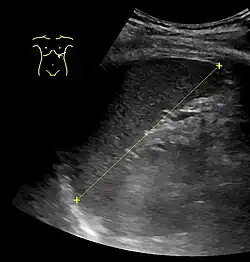

Signs of splenomegaly may include a palpable left upper quadrant abdominal mass or splenic rub. It can be detected on physical examination by using Castell's sign, Traube's space percussion or Nixon's sign, but an ultrasound can be used to confirm diagnosis. In patients where the likelihood of splenomegaly is high, the physical exam is not sufficiently sensitive to detect it; abdominal imaging is indicated in such patients.[11]

In cases of infectious mononucleosis splenomegaly is a common symptom and health care providers may consider using abdominal ultrasonography to get insight into a person's condition.[12] However, because spleen size varies greatly, ultrasonography is not a valid technique for assessing spleen enlargement and should not be used in typical circumstances or to make routine decisions about fitness for playing sports.[12]

Abdominal CT is the most accurate. The spleen needs to be 2–3 times larger than normal to be palpable below the costal margin in physical examination.